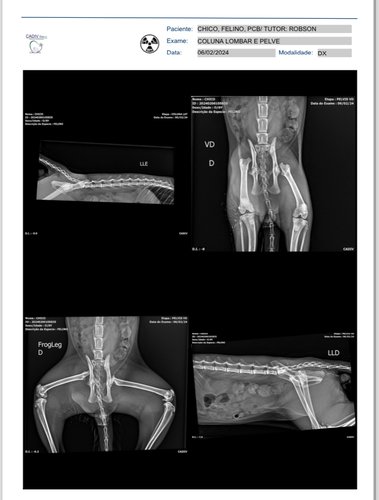

Eu Claudia e meu esposo Robson somos donos do Chico, um felino de 8 meses que infelizmente sofreu um acidente com fratura bilateral na cabeça dos dois Fêmures e precisou de 2 cirurgias. No momento ele fez um lado, e está se recuperando na clínica para então fazer o outro lado. Infelizmente foi em um momento muito delicado para nós tutores, e fizemos essa vakinha como uma maneira de pedir ajuda para custear uma parte do tratamento dele, pois parcelamos tudo. Sempre iremos atualizar o boletim dele aqui!